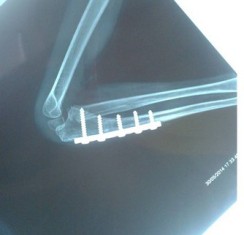

Long bone fractures of children have a very good potential of remodelling. However there are certain criteria which determine the degree of remodelling that takes place. In general, younger children have greater potential of remodelling. Fractures close to joint also have greater potential to remodel. Malunion in the direction of joint axis is better tolerated by patient than rotational malalignment. It is better that fractures are fixed correctly at the time of injury. Reading radiographs of children is difficult and hence a specialist is required.They can be treated with plaster or with nailing and plating. Below are three examples of fracture which were malunited and hence needed to be operated again.

Malunited fractures, in which the bones mend in an incorrect position following a fracture, are the specialty of Dr. Sameer Desai, a top Pediatric Orthopedic Surgeon in Pune. He uses advanced corrective techniques to ensure proper alignment, function, and mobility in children. For expert Malunited Fracture care in Pune, contact Dr. Sameer Desai right now!